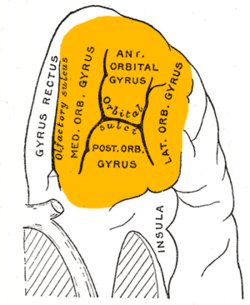

Orbital surface of left frontal lobe. | |